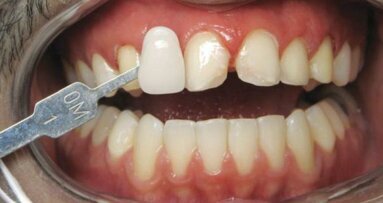

Soyons honnête : il y a des fois où votre prothésiste ne livre pas ce que vous aviez prévu, si clairement, dans votre esprit. Un ...